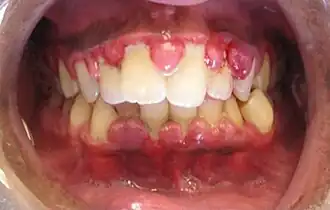

- Signes visibles de la gingivite :

La gencive est rouge, lisse, gonflée ; elle saigne facilement au contact, parfois même spontanément. Une gencive saine doit être rosée, en « peau d'orange », adhérente à l'os sous-jacent.